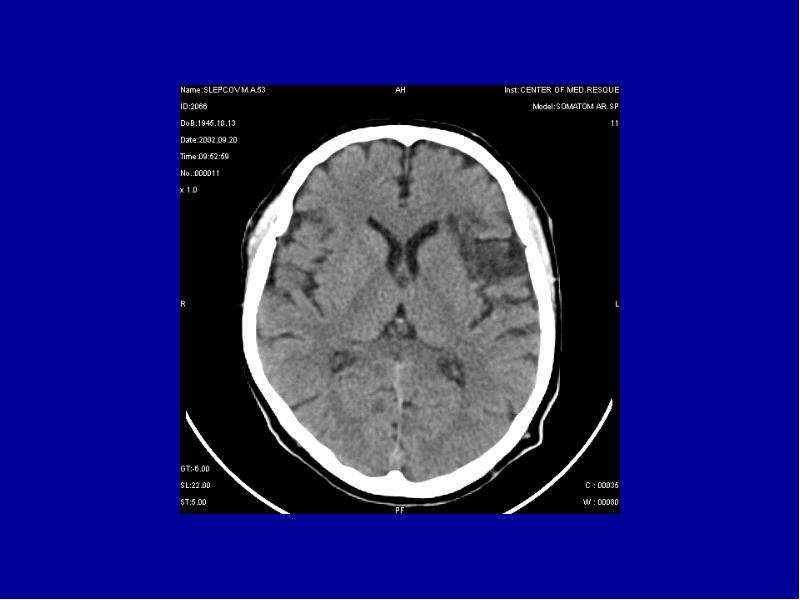

- 9. Физические основы метода Метод КТ основан на оценке поглощающей способности тканей

- 11. Острая субдуральная гематома в правой лобно-теменно-височной области с дислокацией головного мозга